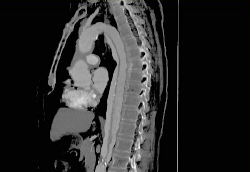

Refer to this picture for question 4. |

4. Systemic association include:

a.

b.

c.

d.

e.